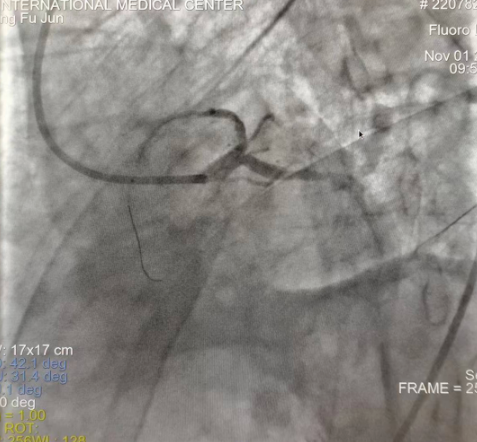

閉塞的血管再通時(shí)間取決于急救時(shí)長、轉(zhuǎn)運(yùn)時(shí)長和治療時(shí)長,在前兩方面,醫(yī)院已為患者爭(zhēng)取了最短時(shí)間?;颊呒覍龠h(yuǎn)在陜北,雖然已在趕來的路上,但最快抵達(dá)西安也要3小時(shí),在與患者家屬電話溝通同意急診手術(shù)后,醫(yī)療總值班代家屬簽字,康曉軍在請(qǐng)示心臟病醫(yī)院王海昌院長及心臟內(nèi)科CCU尚福軍主任后,積極進(jìn)行術(shù)前準(zhǔn)備。在沒有家屬陪同、沒有交費(fèi)、沒有辦入院手續(xù)的情況下,患者經(jīng)胸痛中心綠色通道被送往心臟冠脈介入手術(shù)室,打通了完全閉塞的心臟前降支近段血管。